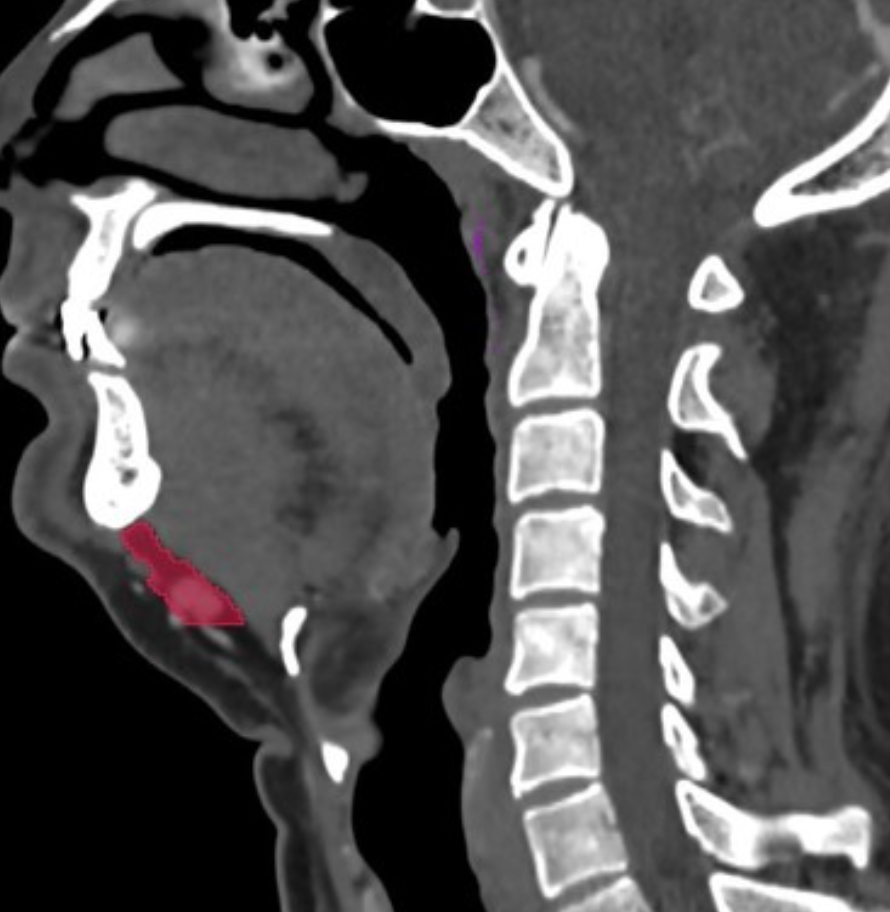

Assessment of proptosis on cross-sectional imaging is difficult and dependant on the study being acquired in the correct plane:

the plane of the study must be parallel to the head of the optic nerve and the lens

the patient must have their eyes open and be looking forward with no eye movement

The reference line for measurement of proptosis is the interzygomatic line (a line is drawn at the anterior portions of the zygomatic bones):

the distance from this line to the posterior sclera is normally 9.9 +/- 1.7 mm 2

the distance from this line to the anterior surface of the globe should be <23 mm 4

The thickness of the extraocular muscles can also be used 1.